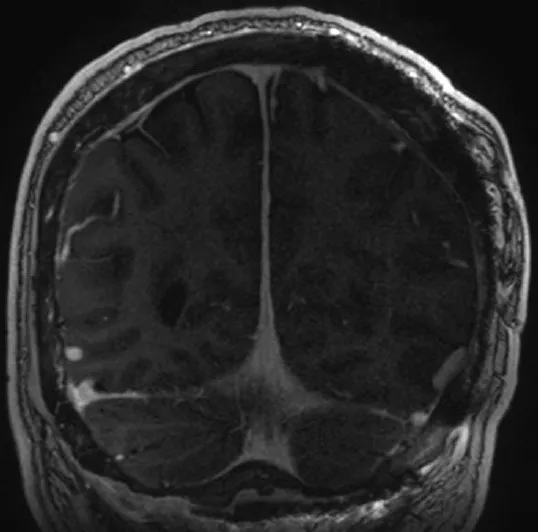

患者术后转入ICU。初期出现视觉障碍伴视力下降,在住院康复期间逐渐改善。最终病理诊断仍为WHO I级脑膜瘤。头胸外固定架持续使用6周。术后6个月随访时,患者可借助老花镜阅读报纸,但术前存在的下方视野偏盲无明显变化。术后18个月常规MRI随访显示无肿瘤复发或再生迹象。

图7.术后18个月冠状位增强T1加权MRI显示跨骨性脑膜瘤已实现全切,未见复发或再生迹象